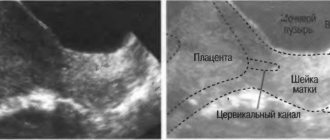

In the 2nd trimester of pregnancy, the examination is performed with a probe through the abdominal wall.

This avoids additional stimulation of uterine activity. If there really is tone, an ultrasound shows that one or all of the walls are under tension - thickened. During diagnosis, the condition of the internal pharynx and cervix is ​​also assessed, which allows us to judge the danger of this condition.